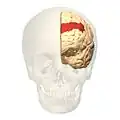

Image

-

Animation.

Animation. -

front view.

front view. -

Lateral view.

Lateral view. -

Medial view.

Medial view.